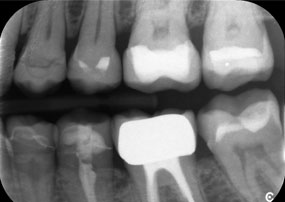

Le défi consistait à retirer douze couronnes splintées en alliage métallique sans endommager les dents piliers sous-jacentes. La pièce à main a été utilisée pour sectionner avec précision les couches de céramique et diviser l'armature métallique à l'aide d'une fraise au carbure, ce qui a permis un retrait minimalement traumatisant des couronnes. En seulement 30 minutes, les anciennes restaurations ont été retirées, permettant la préparation d'une nouvelle prothèse, composée de zircone à contour complet dans la région postérieure et de couronnes facettées dans la région antérieure. Le résultat a été une restauration complète qui a permis d'obtenir un succès tant fonctionnel qu'esthétique (voir fig. 1).

Un deuxième cas illustrant les capacités cliniques du Power Edition concernait le remplacement d'une couronne en zircone endommagée chez une patiente de 63 ans. La patiente présentait une facette ébréchée sur sa couronne en zircone vieille de 20 ans sur la dent 6. Malgré l'emplacement postérieur, la patiente trouvait le défaut gênant et demandait une nouvelle restauration.